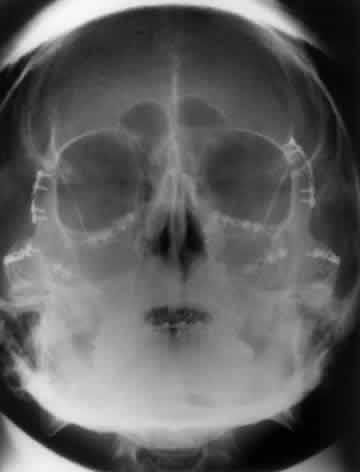

WATERS PROJECTION

In an attempt to improve the visualization of the maxillary and ethmoid sinuses, in 1915 Waters and Waldron7 described a radiographic projection (Fig. 2) that eliminated the overlapping shadows of the dense petrous ridge of the temporal bone. Waters projection is created by placing the chin of the patient on the x-ray cassette with the canthomeatal line (the line that connects the lateral canthus and the external auditory meatus) at 37 degrees to 45 degrees.5,6 This orientation is accomplished if the nose of the patient is approximately 0.5 to 1.5 cm above the x-ray plate.7,8 A mnemonic is—the patient raises the chin up to sip water.

Fig. 2. A. Schematic showing positioning for a Waters projection. (CM, canthomeatal line; CR, central ray) B. Radiograph of a Waters projection. The petrous ridge lies below the maxillary sinus. (a, frontal sinus; b, medial orbital wall; c, innominate line; d, inferior orbital rim; e, orbital floor; f, maxillary antrum; g, superior orbital fissure; h, zygomatic-frontal suture; i, zygomatic arch) (A; Rao VM, Gonzalez CF: Plain film radiography and polytomography of the orbit. In Gonzalez CF, Becker MH, Flanagan JC [eds]: Diagnostic Imaging in Ophthalmology, pp 1–7. New York, Springer Verlag, 1986)

Waters view provides the best image of the maxillary antrum and good images of the orbital rim, orbital floor, zygomatic bones and arches, lesser wing of the sphenoid, and infraorbital foramen. This view is useful to the clinician in orbital floor fracture assessment because of the clear image of the orbital floor and the underlying maxillary sinus. The floor of the orbit should form a continuous radiographic line with the lateral wall of the orbit. Confusion can occur regarding the location of the orbital floor and its relationship to the orbital rim. The orbital floor is located inferior to the orbital rim not in the same plane, because of the orientation of the patient's head in Waters projection. A soft tissue density in the roof of the maxillary sinus or opacification of the floor of the sinus suggests an orbital floor disruption.